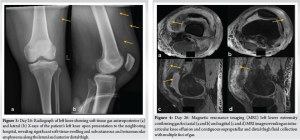

Radiographs of the knee revealed distal thigh subcutaneous and intramuscular emphysema (Fig. 3). MRI of the knee revealed a knee effusion, distal thigh fluid collections, and significant gas foci (Fig. 4). CT of the thigh also exhibited large multiseptated fluid collections in the anterior compartment of the thigh, gas to the level of the greater trochanter along fascial planes, a knee effusion, and diffuse soft-tissue edema (Fig. 5). LRINEC score was 9 [11-13]. The patient also complained of new-onset discomfort in the left shoulder and right posterior chest. A chest CT-scan revealed a gas-forming intramuscular abscess in his left infraspinatus muscle and a right posterior chest wall abscess without gas (Fig. 6).